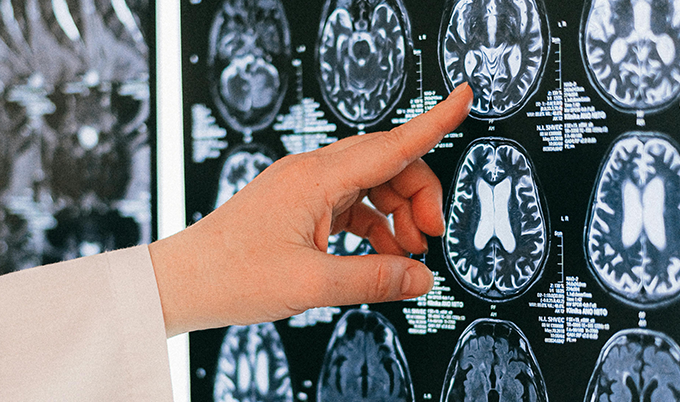

What Does It Look Like on an MRI?

On brain MRI, the condition shows up as white matter hyperintensities — bright spots in the brain’s deep connective tissue, called the white matter. Radiologists may describe them as periventricular changes (clustered near the fluid-filled ventricles), subcortical lesions (distributed deeper in white matter), or lacunar infarcts — pinhole-sized areas of dead tissue where a tiny vessel has fully blocked.

Severity matters. Mild findings in older adults are common and often require monitoring only. Moderate to severe changes — particularly in younger patients, or in anyone whose symptoms are worsening — warrant more active investigation and a real treatment response.